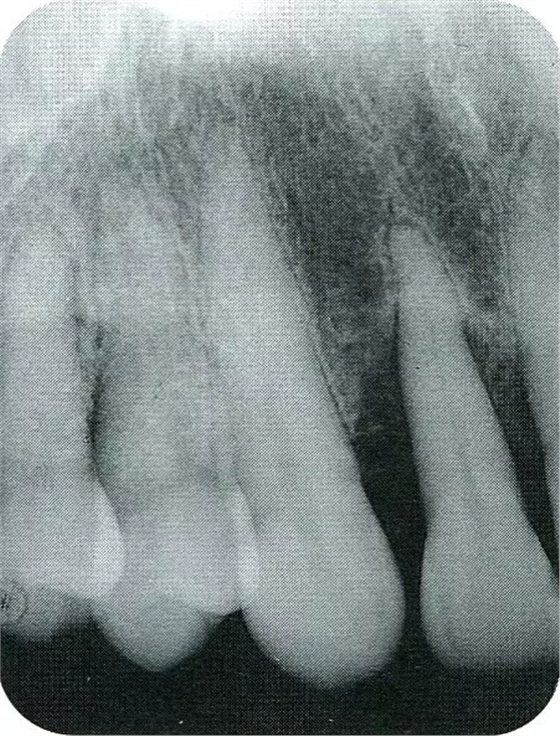

▲圖7-1左下6近中可觀察到3壁性垂直性骨缺損。此病例考慮到齦瓣供血關(guān)系,在前磨牙部位進(jìn)行了減張切開,沒有進(jìn)行縱切開。并利用刮治器、牙周外科用車針進(jìn)行了徹底的骨缺損部位搔刮。

▲圖7-2術(shù)前x片。確認(rèn)存在垂直性深骨缺損。